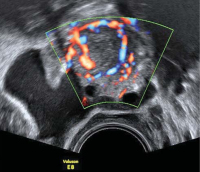

Tipps und Tricks im Gyn-Ultraschall: Sonographische Kennzeichen des Corpus luteum

Journal für Gynäkologische Endokrinologie 2013; 7 (4) (Ausgabe für Österreich): 24-26 Journal für Gynäkologische Endokrinologie 2013; 7 (4) (Ausgabe für Schweiz): 28-30 Volltext (PDF) Abbildungen